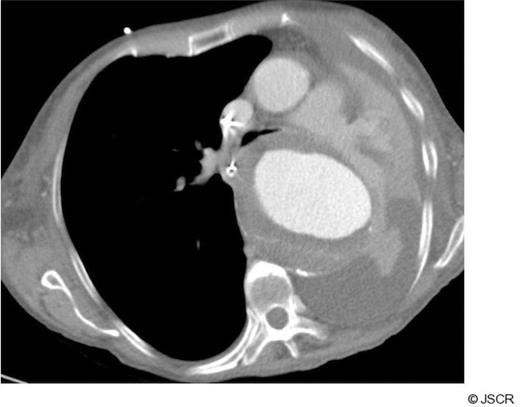

A 77 year old lady presented after an episode of chest pain and dyspnoea. Clinical examination was unremarkable apart from a low grade temperature of 37.8 oC and breath sounds were equal bilaterally. There was no evidence of cardiac ischaemia on an electrocardiogram. Inflammatory markers (white cell count and C-reactive protein) were raised. The cardiac enzyme levels were within normal limits. Empirical antibiotic therapy was instituted for a clinical diagnosis of lower respiratory tract infection. After admission the patient's condition deteriorated with increasing dyspnoea and a worsening PaO2 / FiO2 ratio. Her chest radiograph showed a complete “white-out” of her left lung field (Fig 1). Her trachea was intubated and her lungs mechanically ventilated.

CT scanning revealed a large descending thoracic aortic aneurysm measuring 8 cm in maximum diameter (Fig 2). The left main bronchus was compressed between the aneurysm and the aortic trunk (Fig 3). The patient was regarded as unfit for an open replacement of the aneurysm. The neck of the aneurysm was markedly conical immediately distal to the left subclavian artery, so proximal stent graft placement would have necessitated left common carotid artery and left subclavian artery bypass grafting to provide a parallel proximal landing zone. The distal neck was also markedly conical with a diameter of 42 mm at the coeliac axis, with extensive mural thrombus. These features rendered a successful endovascular repair unlikely, and therefore endovascular interventional was discounted.

CT chest showing complete compression of left main bronchus by large aortic aneurysm